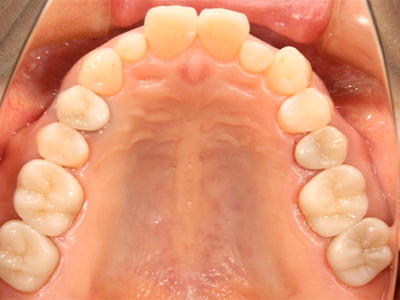

全顎修復

治療前後写真

治療前

治療後

年齢・性別

43歳・女性

来院理由

銀歯を白い歯に治したい

治療内容

マイクロスコープ下でカリエス除去後、セラミック(インレー・クラウン・ラミネートべニア)で全顎的に修復しメンテ移行

治療期間

約2ヶ月

費用

- ラミネートべニア(2本)297,000円

- セラミックインレー(2歯)143,000円

- セラミッククラウン(6歯)1,023,000円

リスク・副作用

再補綴時の歯髄損傷リスク

残存歯質が少ない場合の破折リスク

医院コメント

色・形態・咬合を総合的に整え、審美性と機能性のバランスを長期目線で最適化。